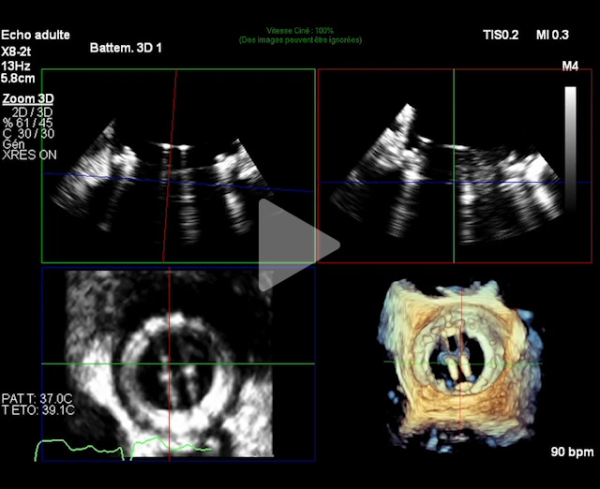

- ETT de sortie : élévation du gradient transmitral avec aspect de blocage d'une ailette mitrale (latérale - vers l'ancienne commissure antérieure)

ETT + ETO

Figure 1

Vidéo 1

Vidéo 2

Vidéo 3